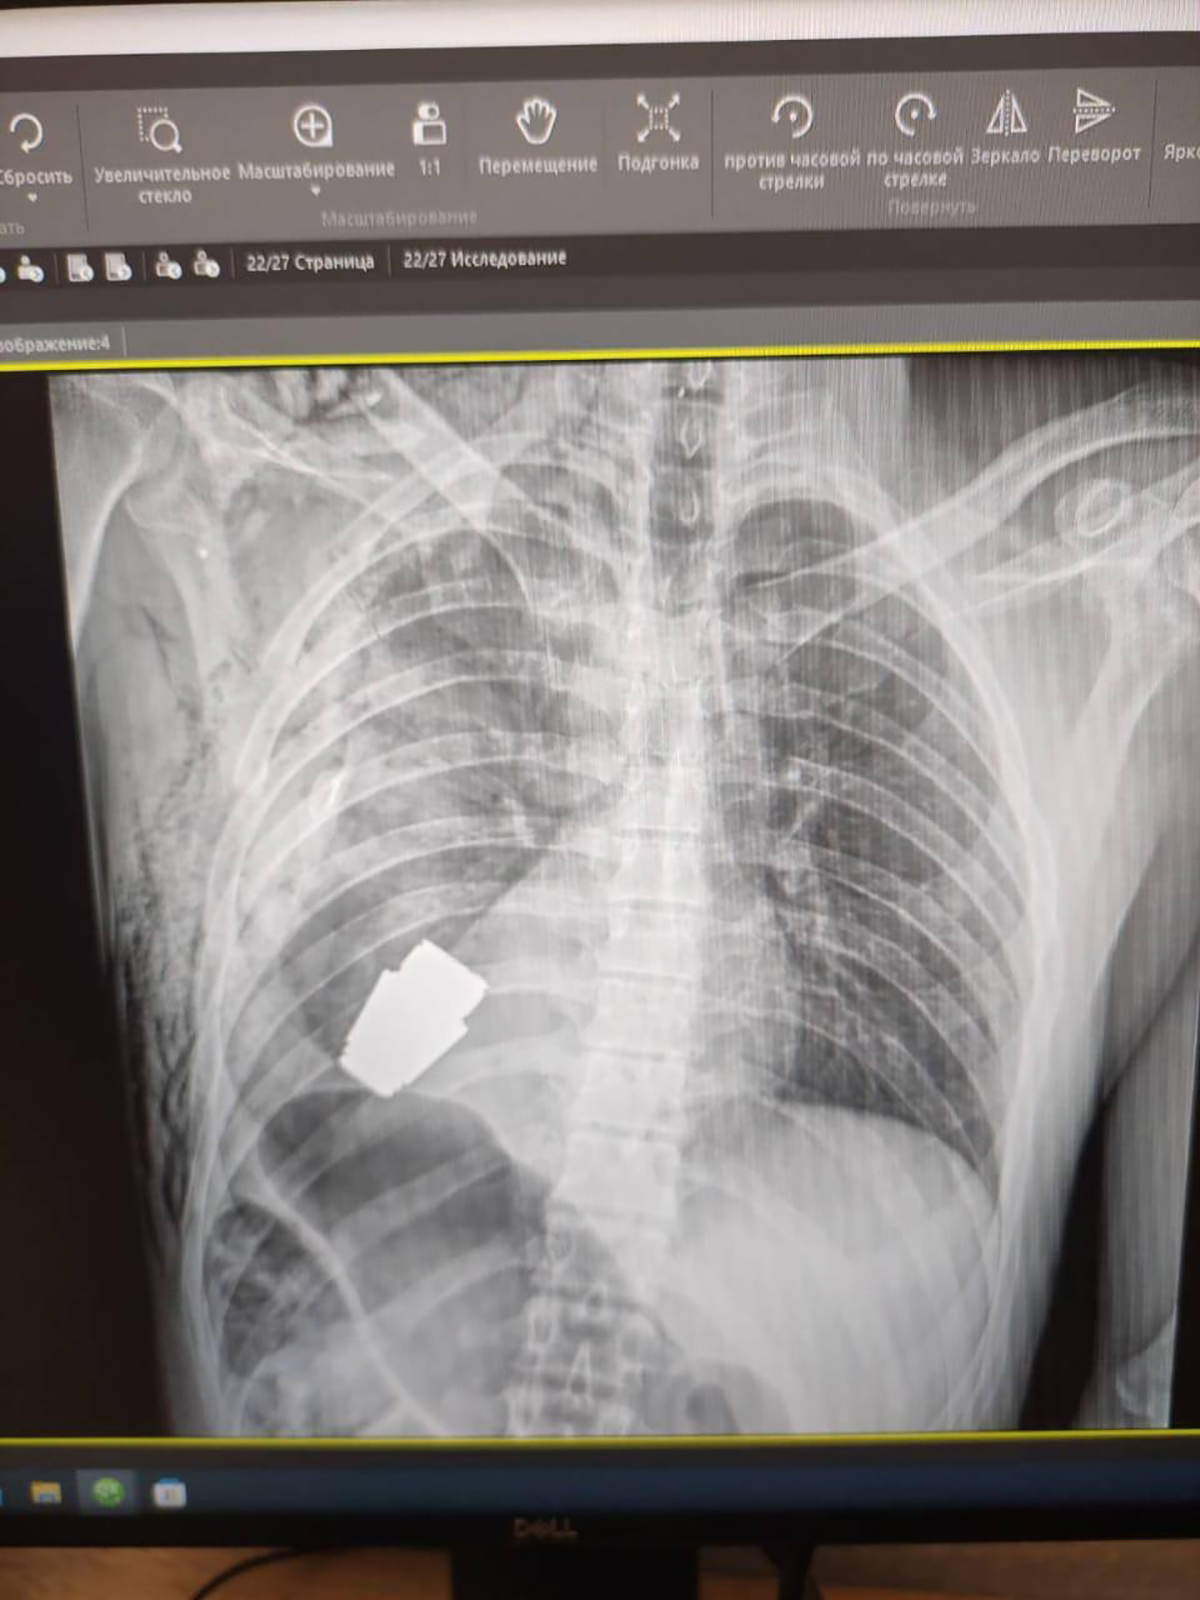

Ukrayna’da bir askerin kalbine yakın bölgesinde patlamamış VOG el bombası tespit edildi. Bombanın her an patlayabilme ihtimali olduğu için Ukrayna Silahlı Kuvvetlerinin en deneyimli cerrahlarından biri olan Andrii Verba tarafından acil bir operasyon gerçekleştirildi.

Ukrayna Savunma Bakanı Yardımcısı Hanna Maliar, cerrahi müdahalenin başarılı olduğunu ve askerin tedavi altına alındığını söyledi.